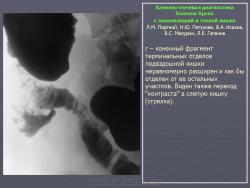

В дифференциально-диагностическом плане интересно -